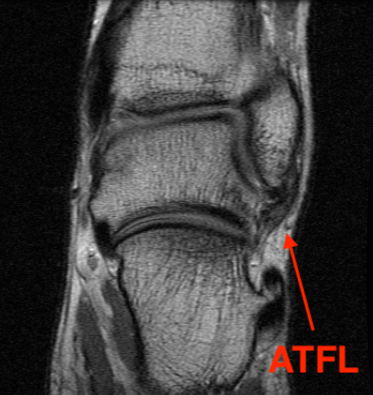

MRI

ATFL normal

Torn ATFL